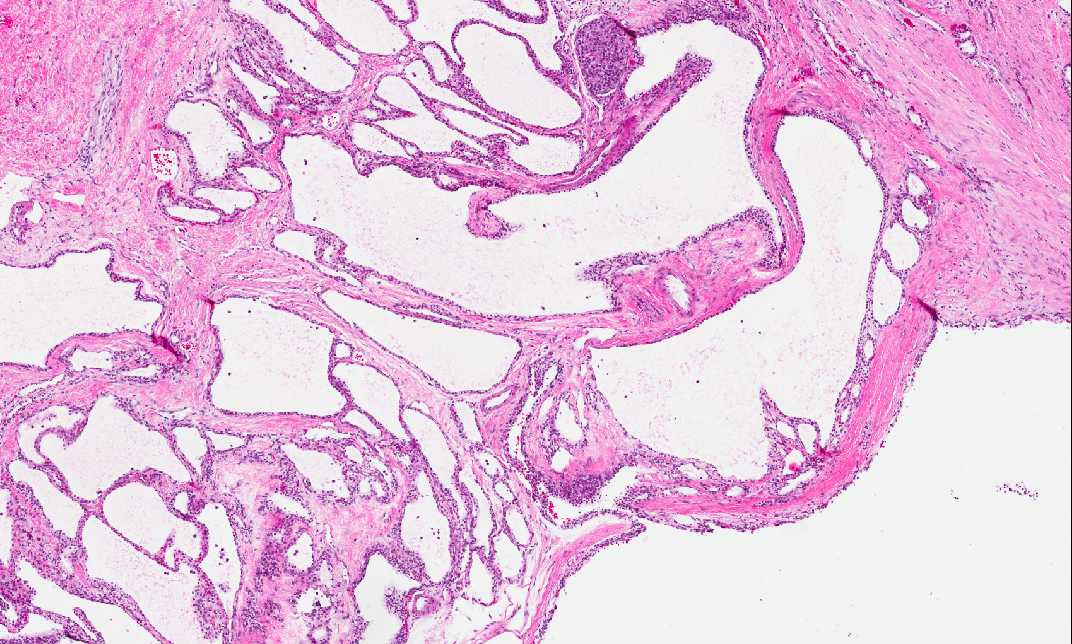

Area 3: The tumor is composed of numerous cysts of variable size separated by fibrous septa of variable thickness lined by a single layer of cuboidal clear cells with bland nuclei. Entrapped islets may be seen within the septa but they are not present in this case. In some areas, the lining seems to have more than one layer and most of these areas are due to tangential cut of the cysts.

• The lesion is outlined by the arrows. Grossly, it appears a well demarcated lesion with a sponge-like cut surface. Histologically, the tumor is composed of numerous cysts of variable sizes which reflect the sponge-like cut surface (Area 3). The lining cells of the cysts are small cuboidal clear cells often with clear cytoplasm, well-defined cytoplasmic borders, and small round nuclei with dense and rather homogeneous chromatin. The lining is usually single layered.

• The clear cells contains glycogen which can be demonstrated by periodic acid Schiff stain. Serous tumors do not produce mucin.

• The size of the cysts in serous cystic tumor of the pancreas can vary from  macrocystic (more common in man), microcystic (more common in woman), and even solid.